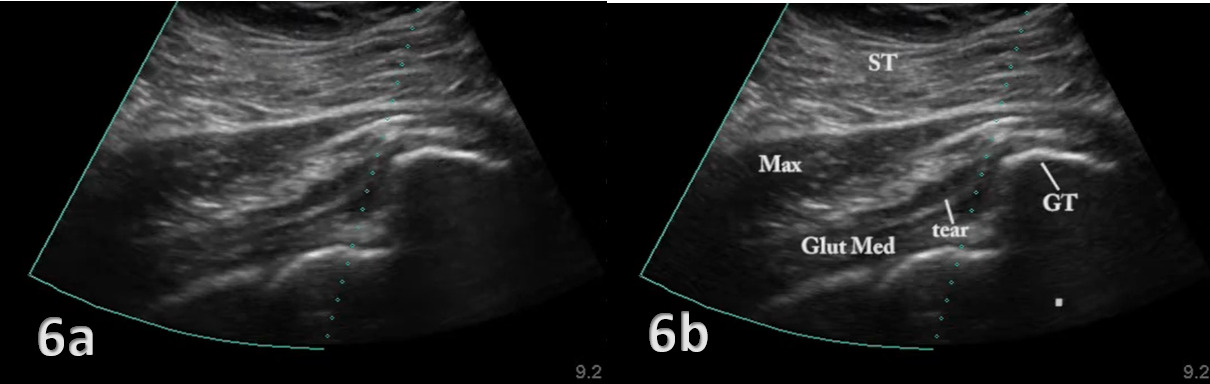

The evaluation of the gluteus medius tendon with MSKUS begins with the patient in a lateral decubitus or standing position, targeting the lateral aspect of the hip. The normal gluteus medius tendon appears as a fan shaped fibrillar structure composed of hyperechoic, striated fascicles with bright, linear bands running within the muscle.2 Pathological changes such as tendinopathy are characterized by hypoechoic (darker) regions within the tendon, tendon thickening, and loss of the normal fibrillar pattern. Tears are identified by discontinuity in the tendon fibers, with partial tears showing as anechoic (black) areas and complete tears as a full separation of the tendon from its insertion.